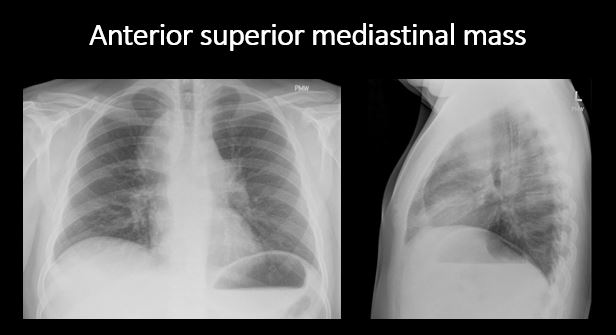

Section 1 Submit Findings Case322 Findings Technique The exam is expiratory, rotated, over or under penetrated, or limited by overlying structures or soft tissues, body habitus, patient positioning, or motion. Yes No Support Devices There is a vascular line or lines present in an abnormal location or otherwise abnormal. Yes No There are other devices such as a chest tube or pleural drain, feeding, NG, or gastrostomy tube, LVAD or pacemaker, vascular stents, cardiac valves, anesthesia catheter, VP shunt, neurostimulator, or other drains or tubes present that are in an abnormal position or are otherwise abnormal. Yes No Cardiomediastinum The superior mediastinum is abnormally widened considering the technique. Yes No There is abnormal shift of the mediastinum. Yes No There is a mass or other abnormal density in or overlying the mediastinum. Yes No There is an abnormality in the retrosternal, retrotracheal, or retrocardiac space on the lateral view. Yes No There is abnormal tracheal deviation or narrowing on the frontal and/or lateral view. Yes No There is pneumomediastinum and/or pneumopericardium. Yes No There is enlargement of the cardiac silhouette. Yes No The heart borders are abnormal. Yes No The right paratracheal stripe is thickened or enlarged. Yes No The azygoesophageal recess is displaced or otherwise obscured. Yes No Vasculature and Hila The aorta is dilated, tortuous, ectatic, calcified, or there is a focal contour abnormality. Yes No The central pulmonary arteries or hila are enlarged. Yes No The aorto-pulmonary window is convex or obscured by a mass, adenopathy, or vasculature. Yes No There is cephalization or haziness of the pulmonary vessels or congestion of the central pulmonary vasculature. Yes No Lungs The lungs are hyperinflated or underinflated generally or segmentally. Yes No There is focal, multifocal, or diffuse airspace disease, mass, opacity, or nodularity. Yes No There is focal or diffuse interstitial disease. Yes No There is focal or lobar atelectasis or total collapse of the lung. Yes No There is cavitary or cystic disease with or without air fluid levels or soft tissue nodularity. Yes No The position of the major and minor fissures is abnormal. Yes No The right or left hemidiaphragm is focally or diffusely obscured on the frontal and/or lateral view. Yes No There is elevation, depression, or contour abnormality of the right or left hemidiaphragm. Yes No Pleura There is focal or diffuse abnormality of the pleura or chest wall. Yes No There is a pleural effusion, blunting of the costophrenic angle, or posterior sulci. Yes No There is focal fluid in the fissures. Yes No There is asymmetric pleural thickening or capping of the apices. Yes No There is a pneumothorax, hydro/pneumothorax, or hemo/pneumothorax. Yes No Bones, Soft Tissues, Upper Abdomen The ribs, clavicles, shoulder, spine, or other visualized bones are abnormal. Yes No There is free air beneath the diaphragm. Yes No The bowel or organs of the upper abdomen are abnormal. Yes No There is subcutaneous emphysema, focal or diffuse soft tissue abnormality, radiopaque foreign body, or post-surgical change or hardware. Yes No